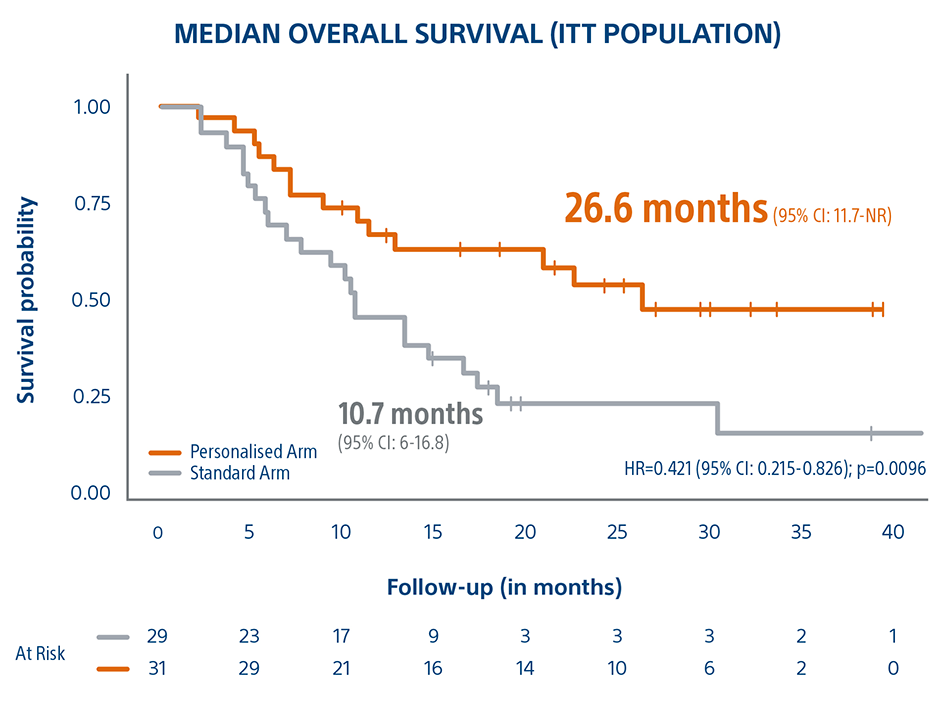

This Level 1 clinical trial demonstrated that personalized TheraSphere dosimetry, using multicompartamental dose administration, achieved a 26.6 month median OS for large tumor HCC patients and a 16-month survival improvement compared to the control arm on standard dosimetry.

Personalized Dosimetry Improves Response